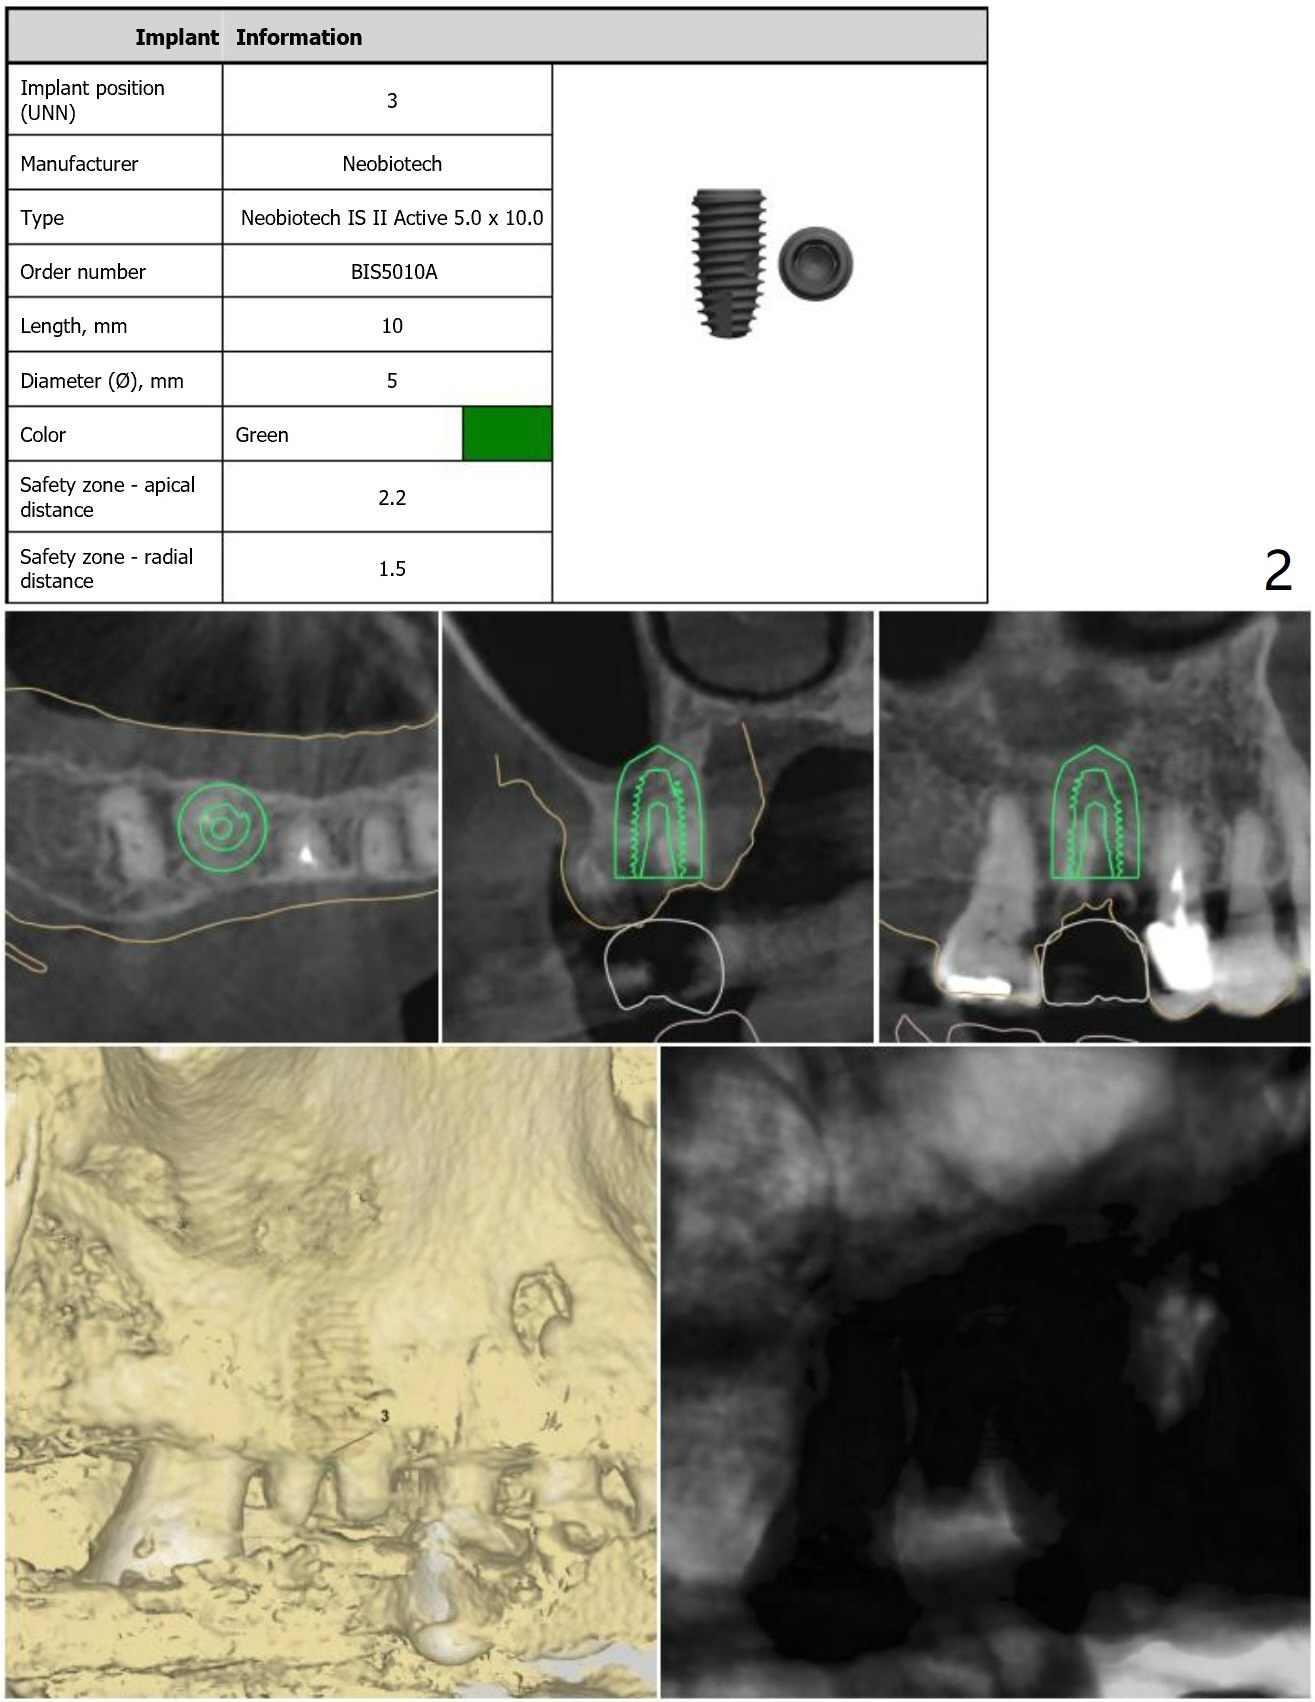

Long Bone Trimmer for #3

Immediate Implant

Molar Immediate Implant,

Prevent Molar Periimplantitis (Protocols,

Table),

Trajectory,